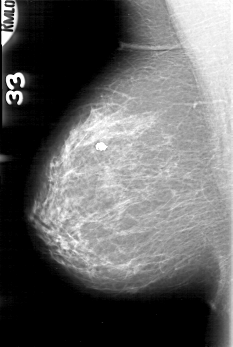

D_4089_1.RIGHT_MLO

RIGHT_MLO LINES 5191 PIXELS_PER_LINE 3481 BITS_PER_PIXEL 12 RESOLUTION 43.5 NON_OVERLAY